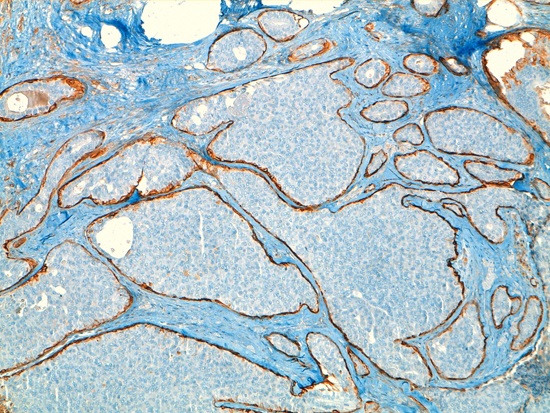

Given the findings, a deferred biopsy was decided upon. Pathology reported the existence of a cystic lesion of 13 mm in the lumpectomy sample. Histological sections showed a cystically dilated duct, neoplastic proliferation within an interior of solid and papillary growth with a delicate fibro vascular stroma and small cells with mild atypia and occasional mitotic figures. In the periphery of the cyst tumorous nests were observed consistent with micro-infiltration areas, and confirmation of the absence of myoepithelial cells with techniques of immunohistochemistry (actin and collagen IV). The immunohistochemistry was positive for hormone receptors (estrogen and progesterone), absence of expression of HER-2 and pof 53 negative. The pathological diagnosis was intracystic papillary carcinoma with solid areas of micro-infiltration but without being able to evaluate the margins of the resection (Fig. 2).